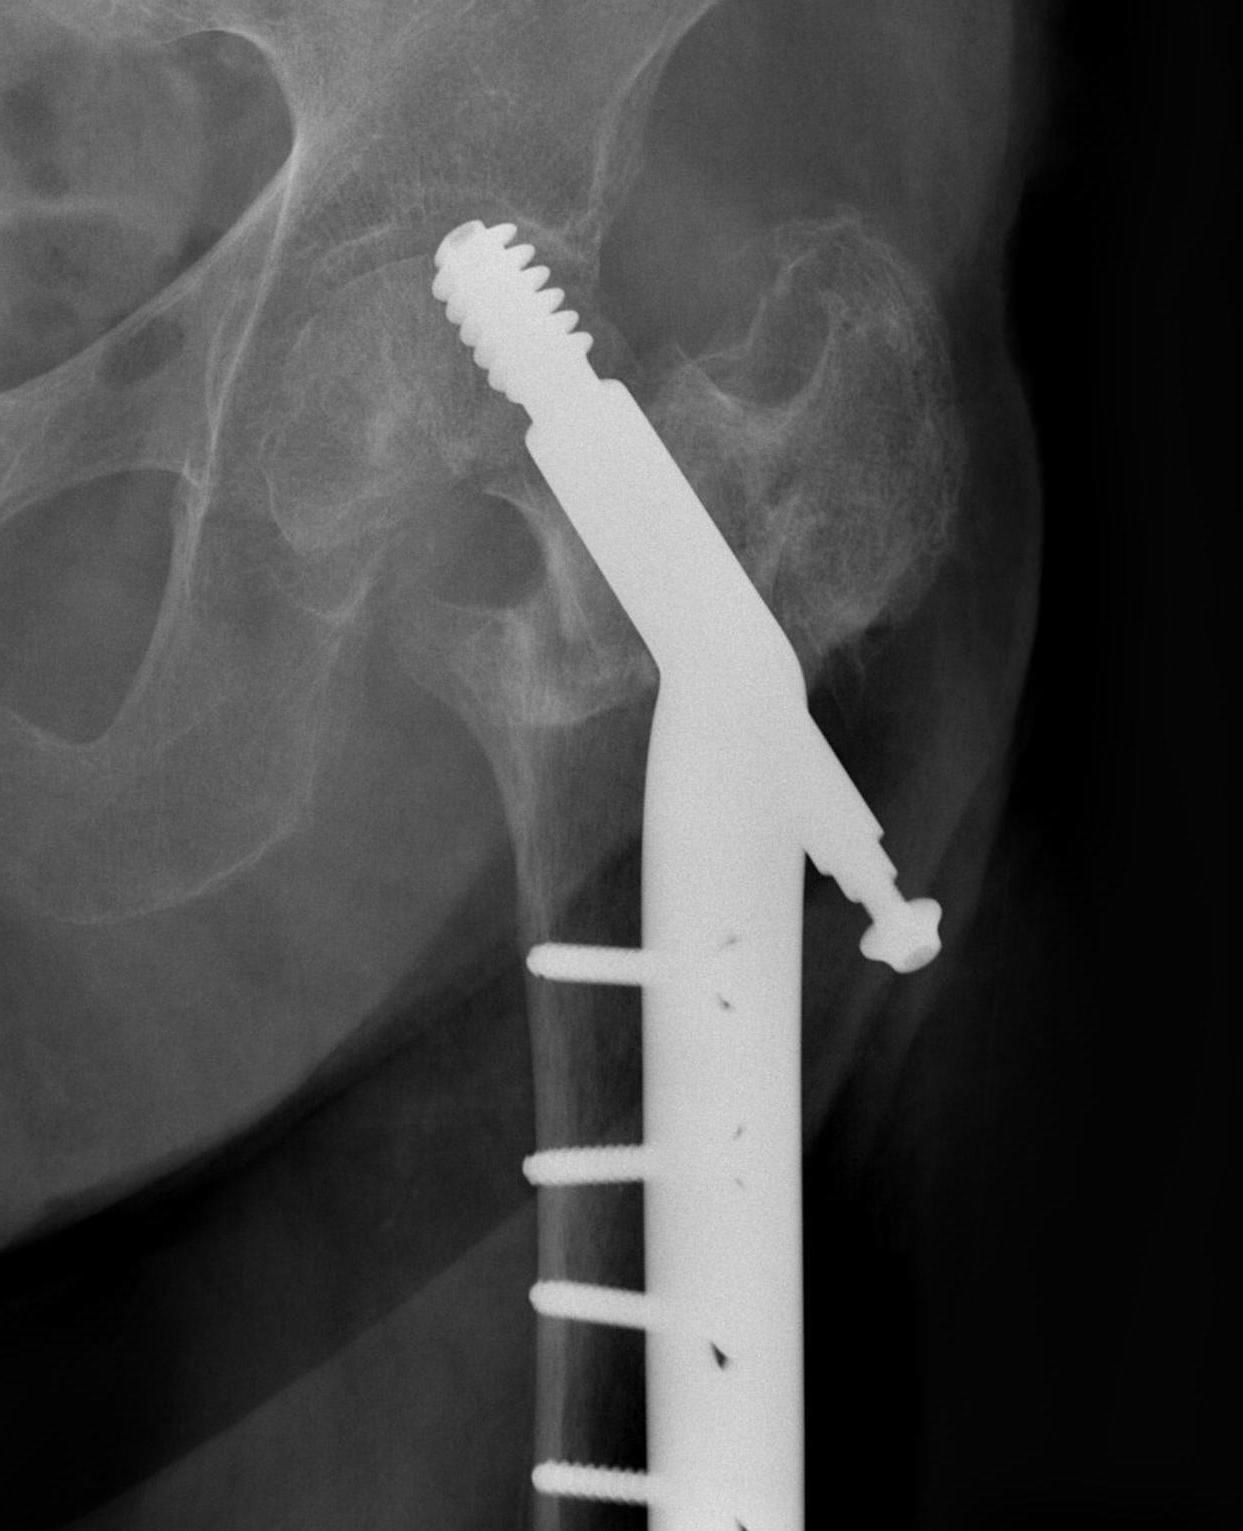

Cephalomedullary nail / Proximal femoral nail

Mechanical advantages

- load sharing rather than load bearing

- decreases lever arm

- supports medial cortex

Surgical advantages

- smaller incision / minimally invasive

- reduced blood loss

- shorter surgical times

Indications

- reverse oblique

- unstable fracture / loss of lateral buttress / loss posteromedial support

- subtrochanteric extension

Single versus dual screws

Yang et al J Orthop Surg Res 2023

- systematic review of single versus dual screw cephalomedullary nail

- 23 studies and 3500 surgeries

- dual screw reduced risk of failure and reoperation

Nail with helical blade vs screw

Kim et al, J Orthop Trauma 2021

- systematic review of 2331 femoral nails

- TFNA neck screw vs helical blade

- helical blade more likely to fail compared to screw (OR 5.33)

- non-union rate same

Long vs short nail

Cinque et al, Arch Orthop Trauma Surg. 2022

- meta-analysis of 3208 intertrochs

- long vs short nail

- short nails had less blood loss, and operative time

- no difference in re-operation, failure, or transfusion rates